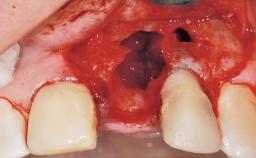

Late Flapless Placement of an Implant in a Maxillary Left Central Incisor Site

A 39-year-old male patient presented with a chief complaint of discomfort and gingival discoloration around his maxillary left central incisor. He was in good general health and was a non-smoker. His past dental history was significant because of the traumatic fracture of tooth 21 in a sporting accident at age 13. Initial dental treatment included endodontic therapy and a full-coverage restoration. The patient became symptomatic 5 years later, when structural failure of the tooth resulted in the dislodgment of the crown. Endodontic retreatment, apical surgery, and post-and-core restoration were performed.

Soft Tissue Anatomy Intact Defective

Bone Volume Deficient horizontally, requiring prior grafting

Bone Augmentation Horizontal|Staged